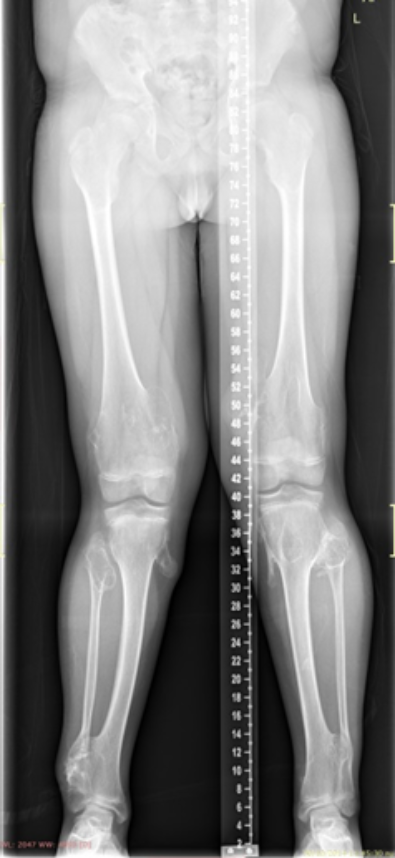

The images show a case of multiple osteochondroma which was operated by

Dr. Zenios in order to restore the mechanical axis.

Pre-operative

Post-operative